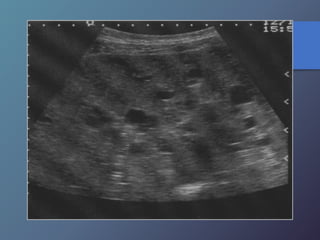

Enfermedad Poliquística

Enfermedades Micoticas

Hepáticas

• Infección secundaria hepática por diseminación

Hematógena de micosis sistémicas (cándidas).

• Inmunosuprimidos.

• Ecográficamente lesión en forma de ojo de toro

(Centro hiperecoico Y anillo hipoecoico), diámetro

De 1-4cm.

• Uniformemente hipoecoica (frecuente por fibrosis

Progresiva).

• Ecogena: calcificación variable por formación de

Cicatriz.